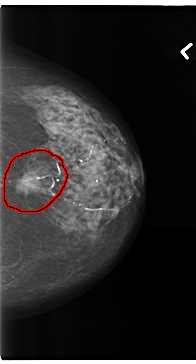

C_0196_1.LEFT_CC

FILE: C_0196_1.LEFT_CC.OVERLAY

TOTAL_ABNORMALITIES 1

ABNORMALITY 1

LESION_TYPE MASS SHAPE OVAL MARGINS SPICULATED

ASSESSMENT 5

SUBTLETY 5

PATHOLOGY MALIGNANT

TOTAL_OUTLINES 1

BOUNDARY